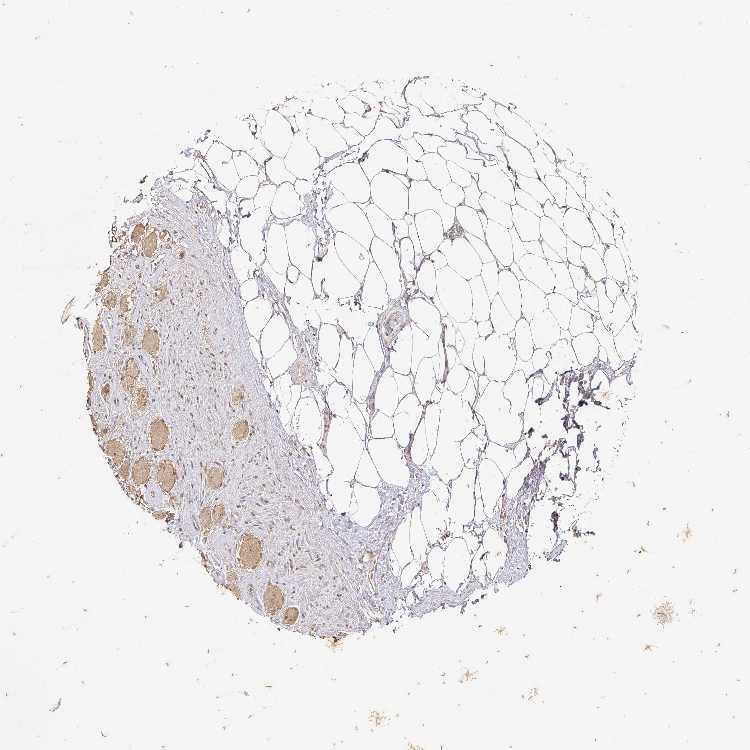

SOFT TISSUE 2 - Antibody stainingi

Antibody staining in the annotated cell types in the current human tissue is reported as not detected, low, medium, or high, based on conventional immunohistochemistry profiling in selected tissues. This score is based on the combination of the staining intensity and fraction of stained cells.

Each image is clickable and will lead to virtual microscopy that enables deeper exploration of all samples and also displays staining intensity scores, fraction scores and subcellular localization as well as patient and tissue information for each sample.

Antibody CAB033237

Fibroblasts Not detected

Peripheral nerve Low